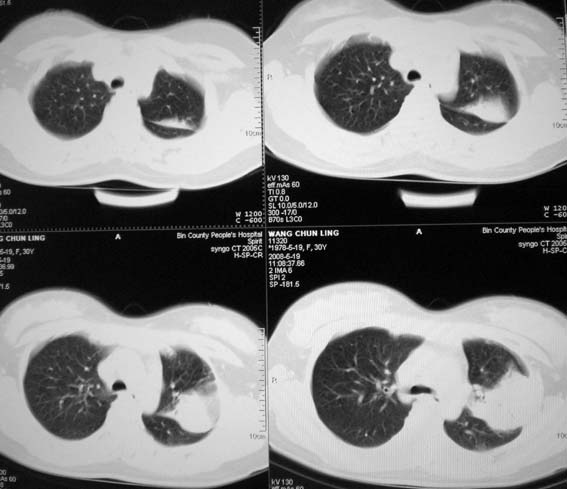

标题: CT13529:肺结核?请会诊!

女,30岁,怀孕后3个月,拍片时肺结核,抗结核治疗4个月复查。

前段支气管通畅,但尖后段支气管闭塞,建议支纤镜除外肺癌,有原片吗,对比一下了。

结核.前段支气管通畅,但尖后段支气管闭塞,建议支纤镜除外肺癌